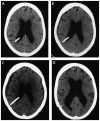

Purpose of review: This article provides neurologists with a pragmatic approach to the diagnosis and treatment of idiopathic normal pressure hydrocephalus (iNPH), including an overview of: (1) key symptoms and examination and radiologic findings; (2) use of appropriate tests to determine the patient's likelihood of shunt responsiveness; (3) appropriate referral to tertiary centers with expertise in complex iNPH; and (4) the contribution of neurologists to the care of patients with iNPH following shunt surgery.

Recent findings: The prevalence of iNPH is higher than previously estimated; however, only a fraction of persons with the disorder receive shunt surgery. iNPH should be considered as a diagnosis for patients with unexplained symmetric gait disturbance, a frontal-subcortical pattern of cognitive impairment, and urinary urge incontinence, whose MRI scans show enlarged ventricles and whose comorbidities are not sufficient to explain their symptoms. Physiologically based tests, such as the tap test (large-volume lumbar puncture) or temporary spinal catheter insertion for external lumbar drainage with gait testing before and after CSF removal, or CSF infusion testing for measurement of CSF outflow resistance, can reliably identify patients who are likely to respond to shunt surgery. Properly selected patients have an 80% to 90% chance of responding to shunt surgery, and all symptoms can improve following shunt surgery. Longitudinal care involves investigating the differential diagnosis of any symptoms that either fail to respond to shunt surgery or that worsen after initial improvement from shunt surgery.